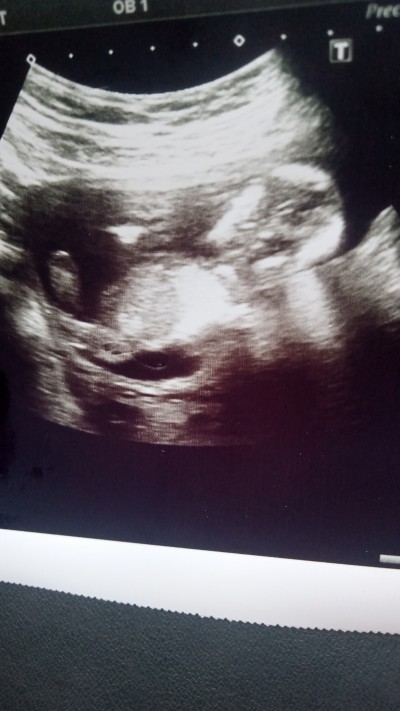

Kızlar 28 haftalık oldum her gittiğim doktor cinsiyeti hakkında başka bir şey söyledi  iki doktor kız iki doktor erkek dedi hep sağ tarafım da sizce nedir?

Gebelik haftası 28